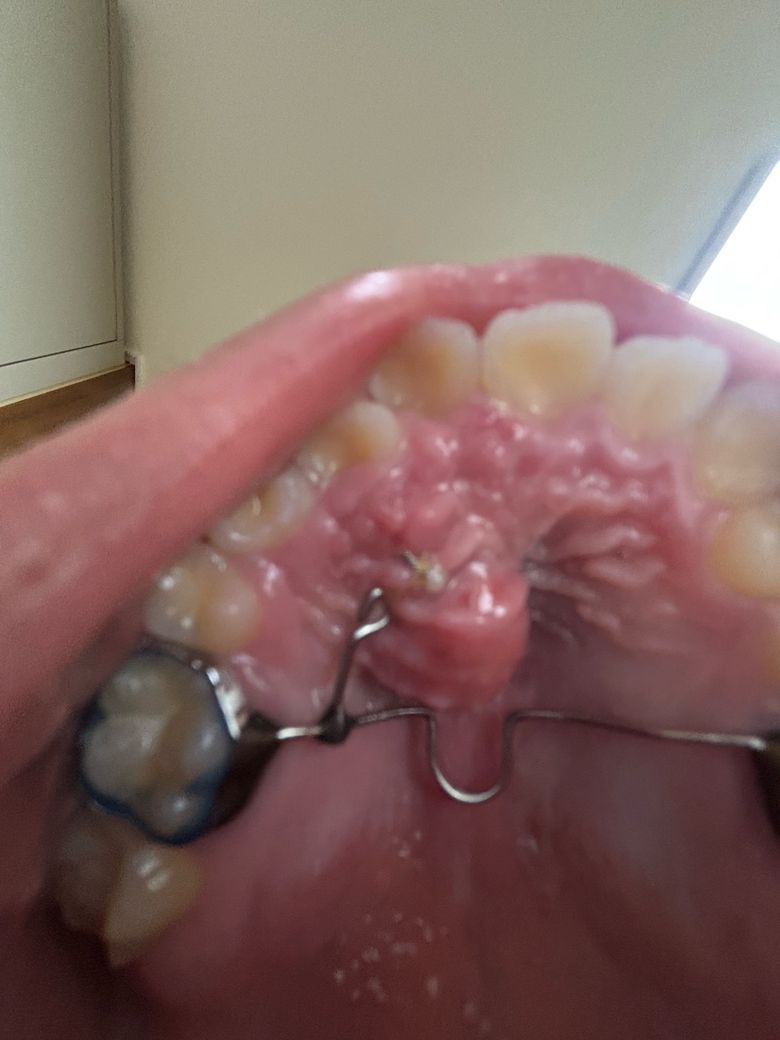

매복치 견인중 입천장이 점점 붓는데 괜찮은 건가요?

제가 매복치 견인을 해야해서 입천장에 장치를 단지 2달이 됬는데요. 근데 갑자기 3일 전부터 입천장이 붓더니 점점 심해져서요. 괜찮은 걸까요?

• 1번 째 사진

사진으로 봤을 경우에는 단순히 견인장치에 의한 자극이 아닌 주변 조직에 농이 찬 것으로 보입니다. 감염등에 의해서 해당 증상이 나타날 수 있으니 치료를 받은 치과에서 진료를 받아보는 것이 좋습니다.

많이 부었네요 보통 장치 주위 위생관리가 잘 안되어 잇몸이 살짝 붓는 경우도 있지만 이런 케이스는 치과가서 조치를 받아야 할 것 같습니다